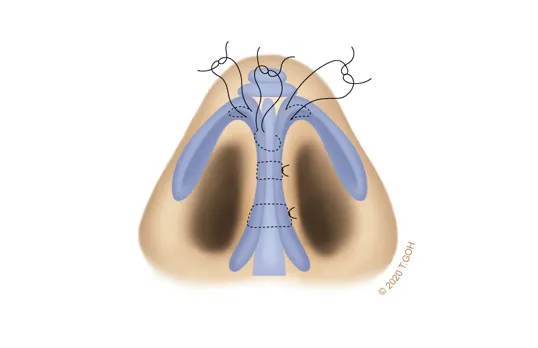

Expert use of fine suture techniques

Absorbable fine sutures are used to reshape the alar cartilages, enhancing projection and sculpting a well-defined tip. This meticulous approach ensures a delicate, refined result achieved through precision and skillful stitching.

In cases of weak or widely splayed lower lateral cartilages, the nasal tip lacks support. Simple onlay grafting alone is insufficient, as the heavy tip may droop or lose shape over time. To address this, the tripod structure must be reinforced with sutures to create a stable tip. Columellar strut grafts may also be required to provide additional support.

A strong foundation is necessary to ensure the nasal tip retains its shape and position over time. By combining cartilage grafts with precise suture techniques, we create a stable nasal tip that is both durable and aesthetically refined.